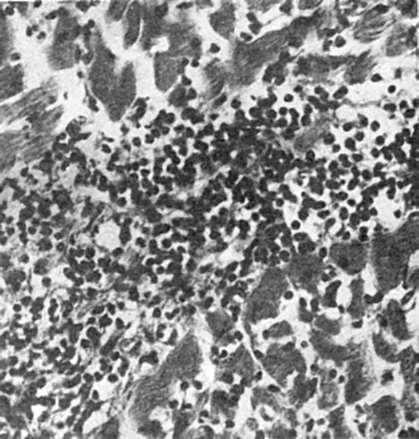

Межуточное (интерстициальное) воспаление. Характеризуется образованием клеточного инфильтрата в строме - миокарда (рис. 70), печени, почек, легких. Инфильтрат может быть представлен гистиоцитами, моноцитами, лимфоцитами, плазматическими клетками, лаброцитами, единичными нейтрофилами, эозинофилами. Прогрессирование межуточного воспаления приводит к развитию зрелой волокнистой соединительной ткани -

развивается склероз (см. схему XII).

Рис. 70. Межуточный

(интерстициальный) миокардит